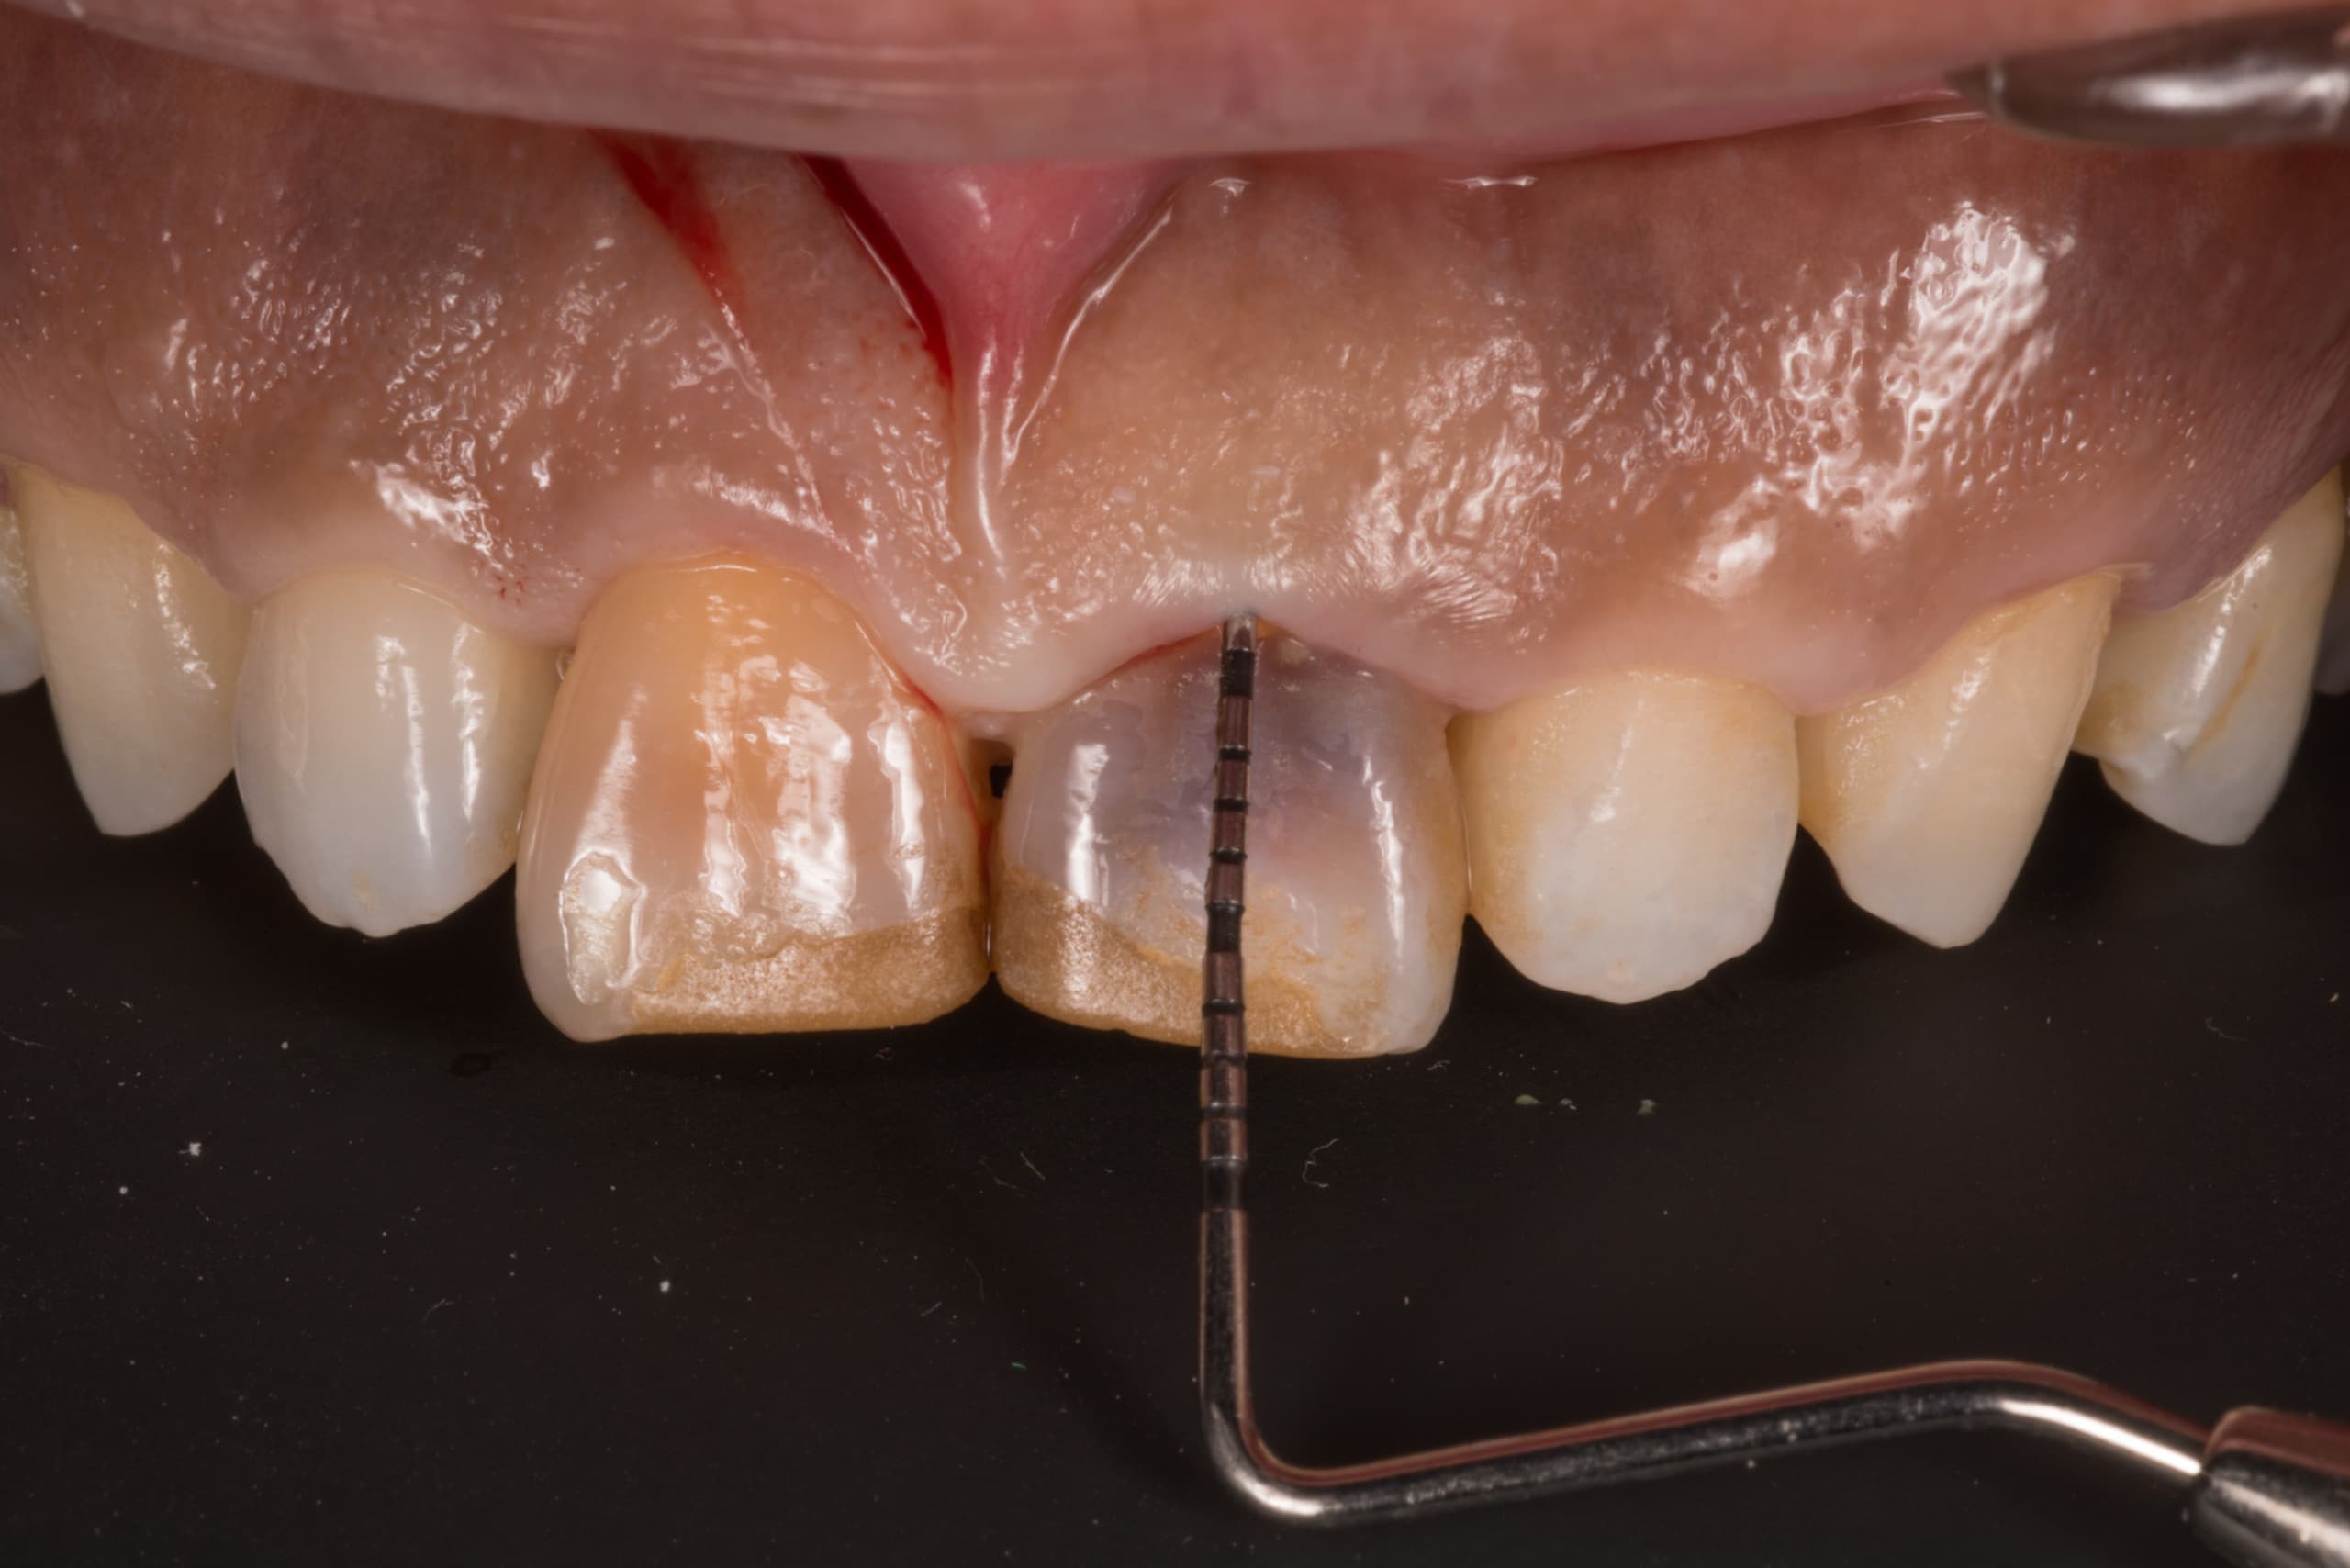

早期発見が重要です

小さな虫歯を放置してはいけません

噛み合わせ、生活習慣などあらゆる原因を調べます